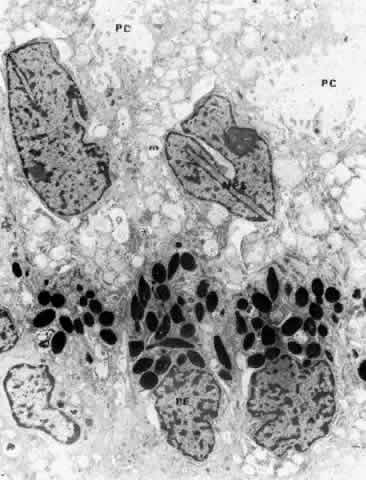

Fig. 19. Evidence of tight junctional complexes in the anterior ciliary epithelium of Macaca mulatta. The pigmented epithelial cells (PC) are outlined by a thin black line that is the reaction product of horeseradish peroxidase, a tracer substance injected intravenously in vivo. The tracer has entered the intercellular spaces of the nonpigmented epithelium (NPC) but is held up by occluding junctions (arrowheads), preventing further progress into the posterior chamber. (X 8450; Courtesy of Dr. Guiseppina Raviola)

The zonula occludens is the primary component of the blood-aqueous barrier “tight junction.” It appears as a focal area at which the bilayered plasmalemmal membranes of each cell surface are tightly joined (Fig. 20). Zonular adherens junctions occur adjacent to occludens junctions on the basal side. They show a 12- to 15-nm space between the adjoining cells, with filamentous matrix material clinging to the cell membranes on either side. By the freeze-fracture technique, the zonula occludens consists of branching anastomosing strands on the cytoplasmic side of the plasmalemmal membrane (P-face) and matching grooves on the external side (E-face), giving a quilted effect (Fig. 21). The variation in number of strands seen from area to area in the ciliary zonula occludens region23 is consistent with physiologic evidence that the NPE is leaky to ions and small molecules, rather than being an absolute barrier like that between the endothelial cells of the retinal vessels. Ohnishi and Kuwabara24 found the tight junctions of the anterior pars plicata had the fewest strands, explaining why this region is so sensitive to leakage after paracentesis in several species.